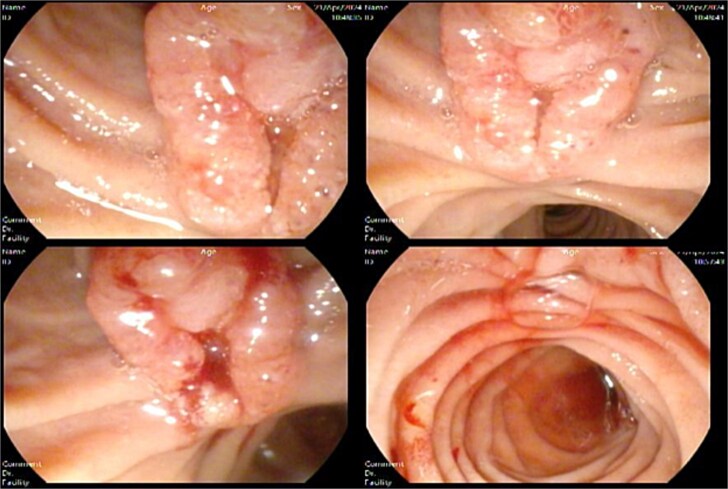

Suspecting malignancy, a side view endoscopy was planned, and tumor markers (AFP, CA 19-9 and CEA) were ordered, which showed an ulcerated ampullary mass of ~1.5 cm in size causing common bile duct obstruction (Fig. 4) and a normal stomach and esophagus.